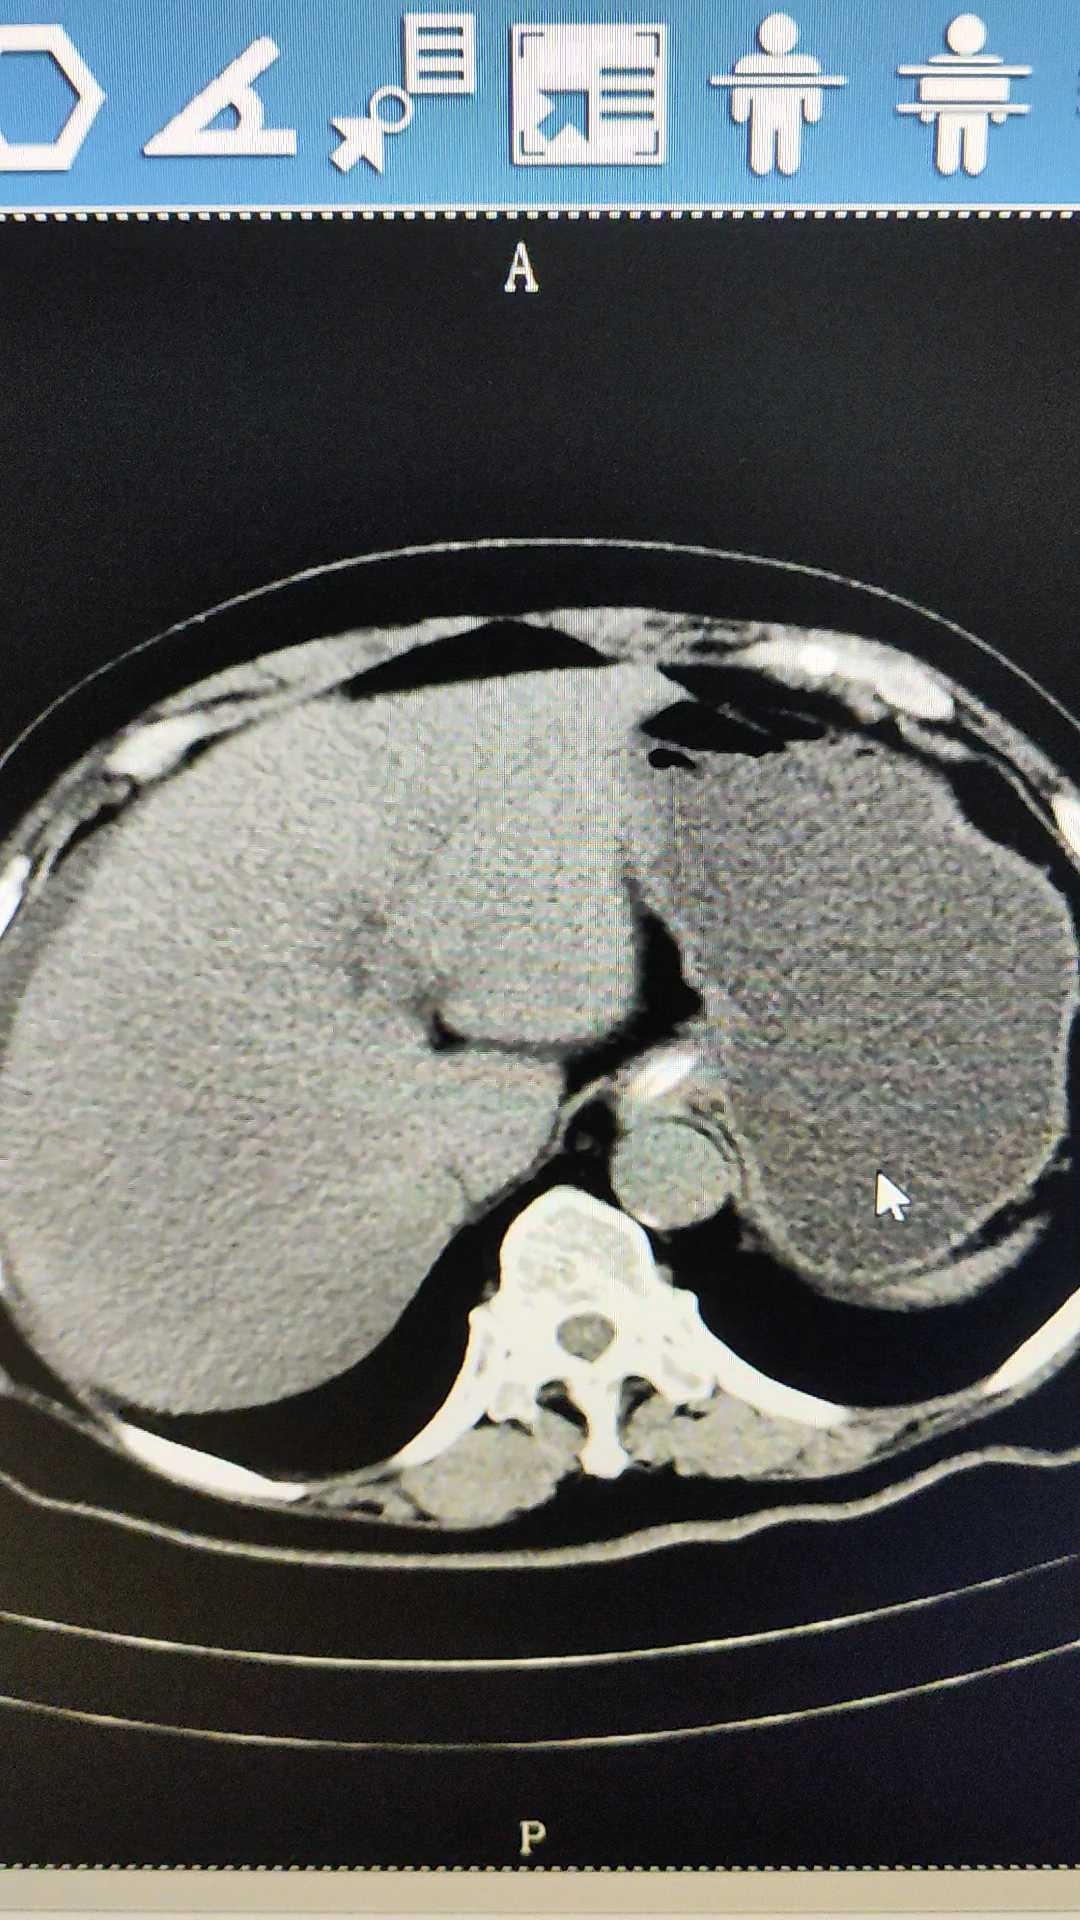

【患者信息】:女,70岁

【主诉】:腹痛1月余,加重一周

【检查】:腹部CT

【临床诊断】:肠梗阻

【治疗经过及结果】:保守治疗无效,切开取石

溶石后柿石从胃进入肠道引起肠梗阻